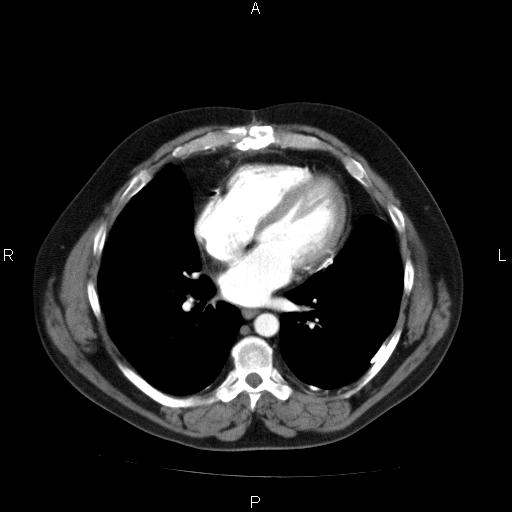

همانطور که در تصویر بالا مشخص شده است بعد از تنظیم و اتمام مراحل تنظیم نمایشگر پکس میتوانید تمام تصاویر را به راحتی با استفاده از این قابلیت مشاهده نمایید.